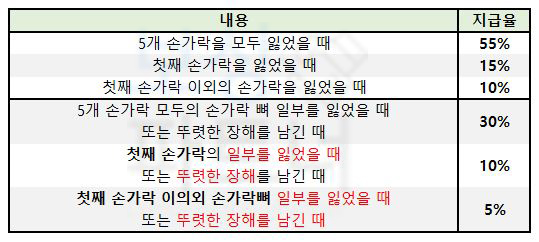

하지만 손가락압궤손상 진단받아 손가락수술하게 되었다면 내가 가입한 보험약관의 장해분류표 및 장해 약관을 보시면 손가락의 장해에 대해 아래와 같이 규정하고 있습니다.

하지만 이 장해 기준만 보고 단순히 “손가락이 안 움직여서” 혹은

“손가락 일부가 절단되어서”

누구나 장해보험금을 받을 수 있는 것이 아닙니다. 실제로 보험 약관 기준에 부합하는 영구 장해를 가지고 있는지, 그 장해를 장해진단서로 증명할 수 있는 부분인지도 후유장해 보험금 지급의 중요한 요인이 됩니다.